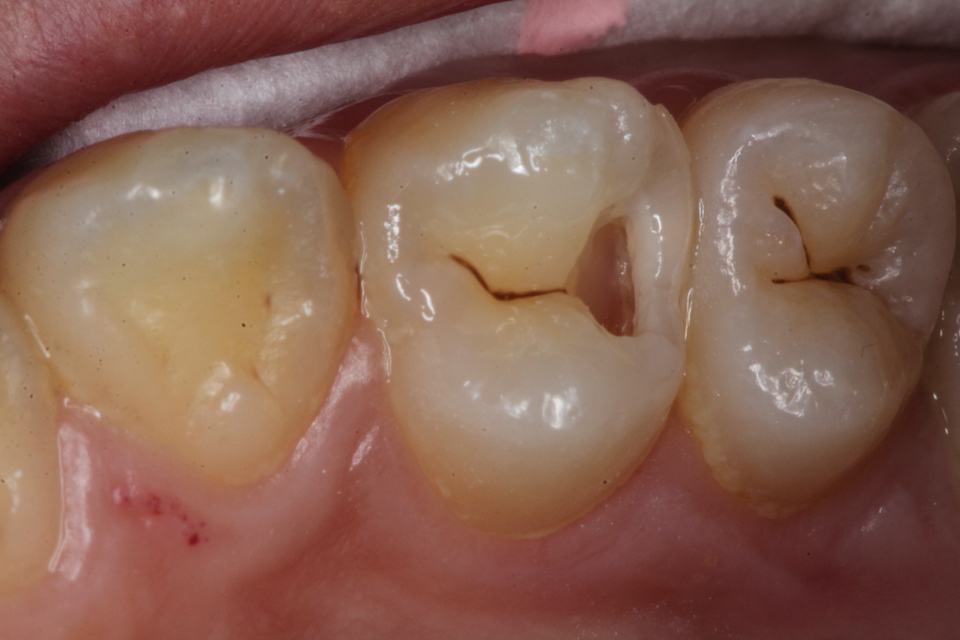

虫歯は金属の錆や腐食と同じ1.42 2025.11.10

虫歯は金属の錆や腐食と同じ1.41 2025.06.05